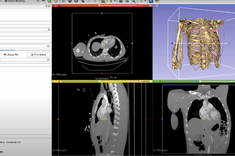

Podczas ostatniego spotkania koła naukowego, wygłoszona została prezentacja pt. “Analiza MES modelu 3D pozyskanej z DICOM”. Przybliżone zostały etapy obróbki formatu DICOM (pozyskanego z badań obrazowych MRI, CT, RTG) do formatu IGES, pozwalającego na wykonanie symulacji numerycznych. Poruszony został także temat użyteczności wykonywania analiz modelów bryłowych w medycynie.

Prezentację przygotowała i wygłosiła Natalia Dudek, studentka Inżynierii Medycznej.